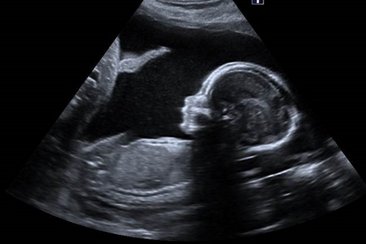

Die Veranstaltung der Klinik für Geburtshilfe und feto-maternale Medizin behandelt die fetale Wachstumsrestriktion – ein hochrelevantes Feld sowohl für die Geburtshilfe als auch für die Neonatologie. Internationale, renommierte Vortragende werden das Thema aus unterschiedlichen Perspektiven beleuchten und neueste wissenschaftliche Erkenntnisse präsentieren.